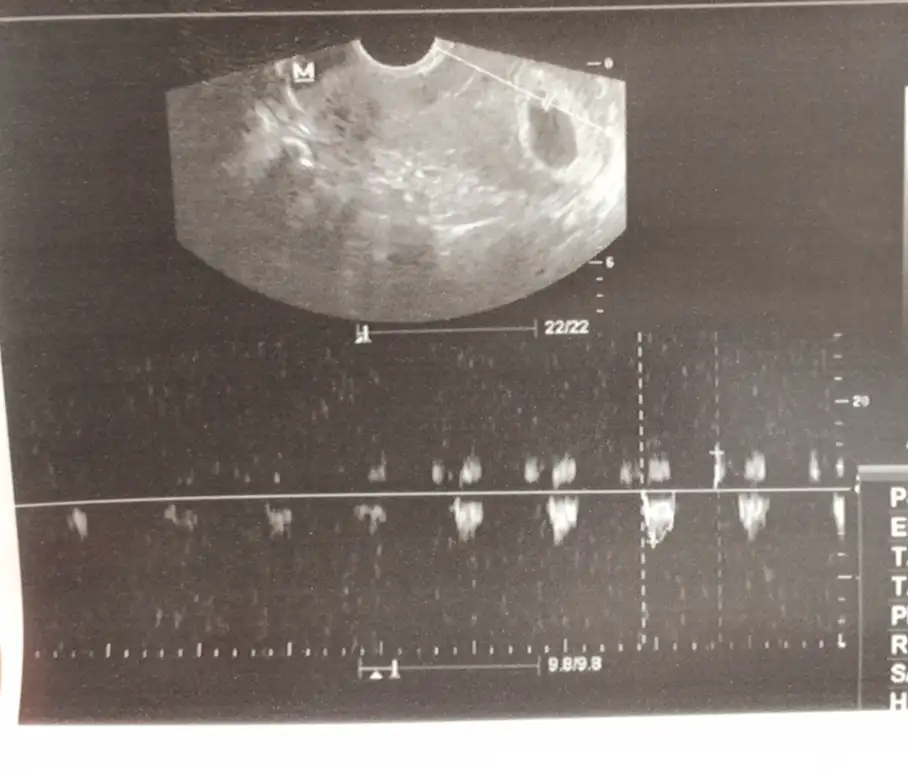

Ay ben sizin attığınız usg fotolarına bakıp aglarım . Benım usg ve bebeşin konumlandıgı yer Ne keseyi anlar burda ınsan ne bebeği Bu arada vajinal baktı.

Ay maşallah teorilere göre bebek erkek valla ben keseyi de bebeği de anladım her şey yolunda mıymış peki